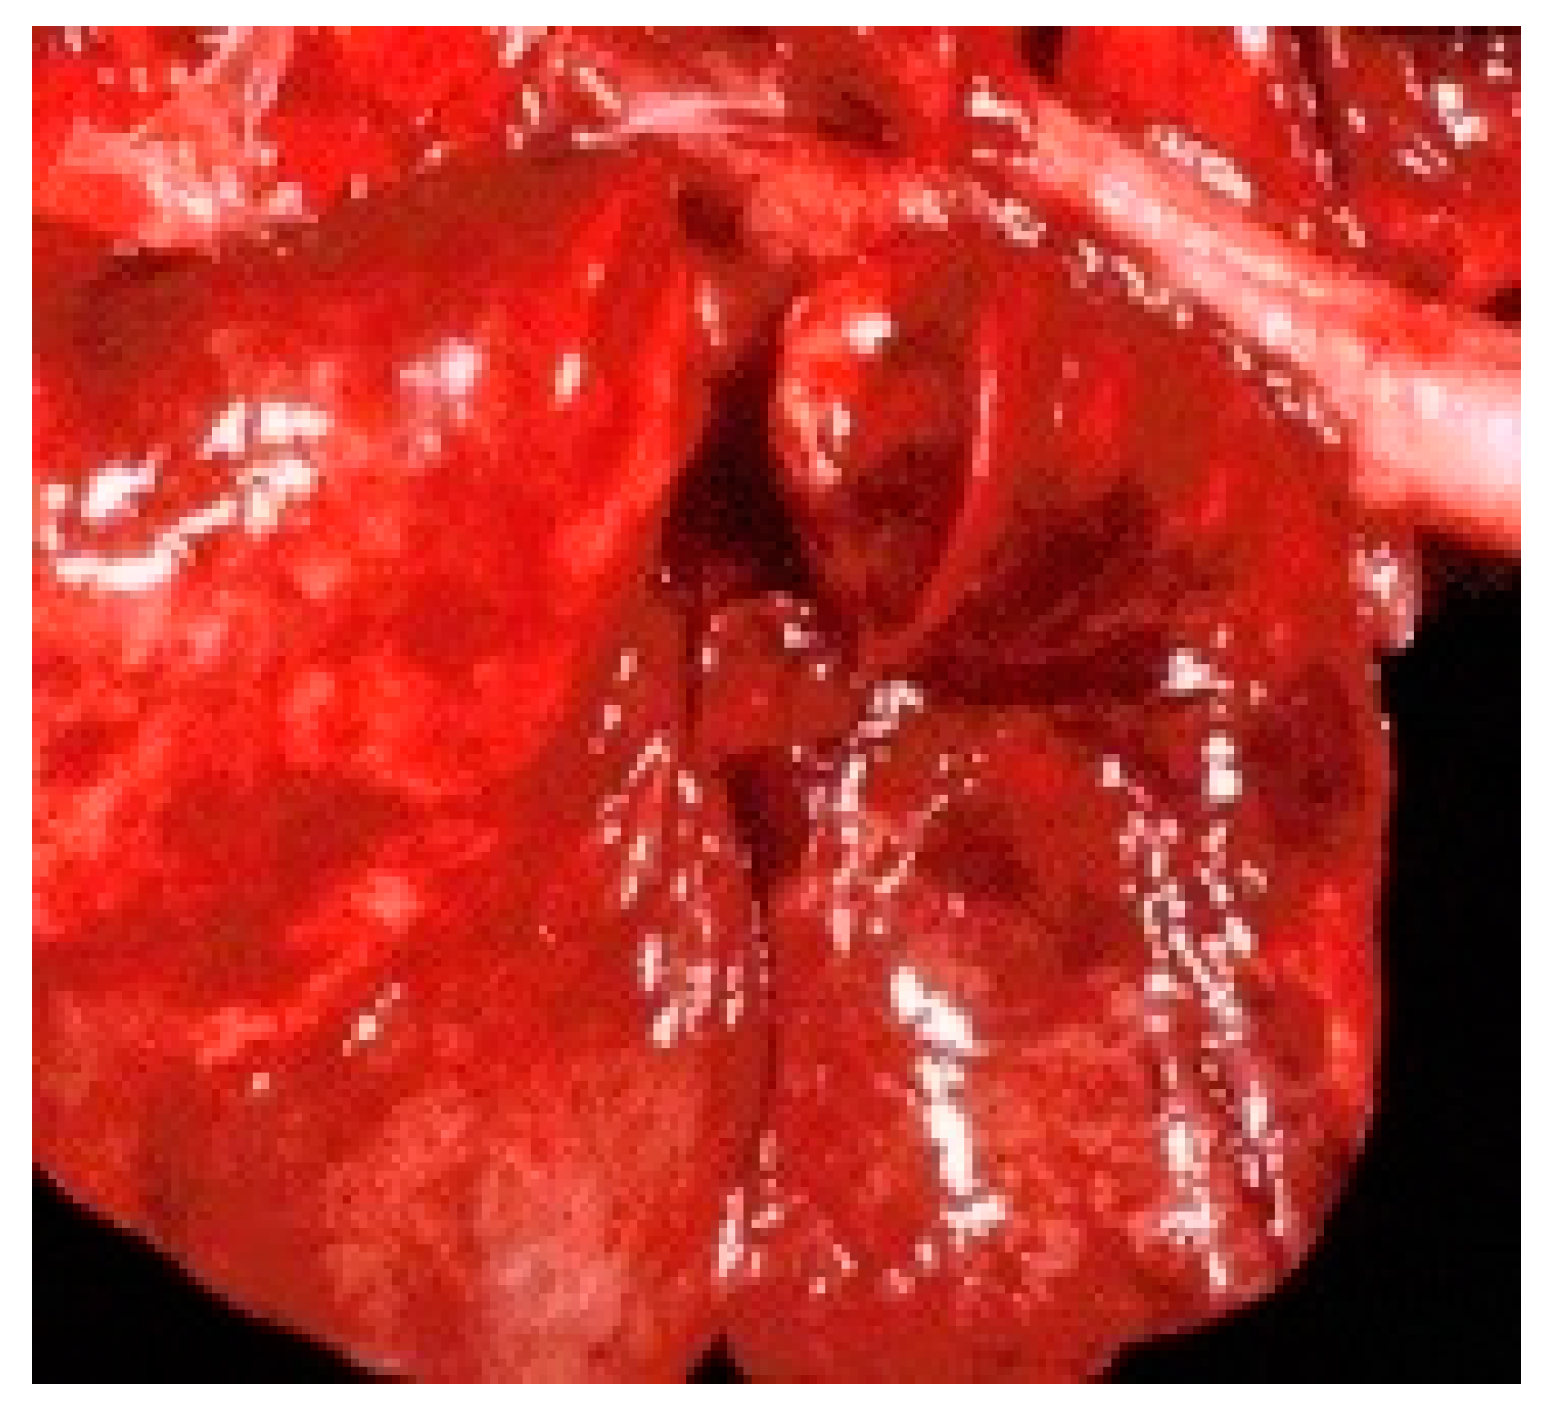

Following the necropsy, several lesions were noted, such as: hemorrhagicgastroenteritis (Figure 1), pulmonary congestion (Figure 2), pharyngeal ulcers, foci of necrosis on the surface of the liver and pancreas. The severity of the clinical signs and the observed anatomo-pathological lesions proved the septicemic evolution of the disease.

Figure 1. Intestine: Gross lesion, enteritis, hyperemia.

Lesions reported during the gross necropsy examination of raccoons included those observed by other researchers in dogs with this disease, e.g., severe dehydration due to severe enteric phenomena, pulmonary congestion, hemorrhagic enteritis [24].